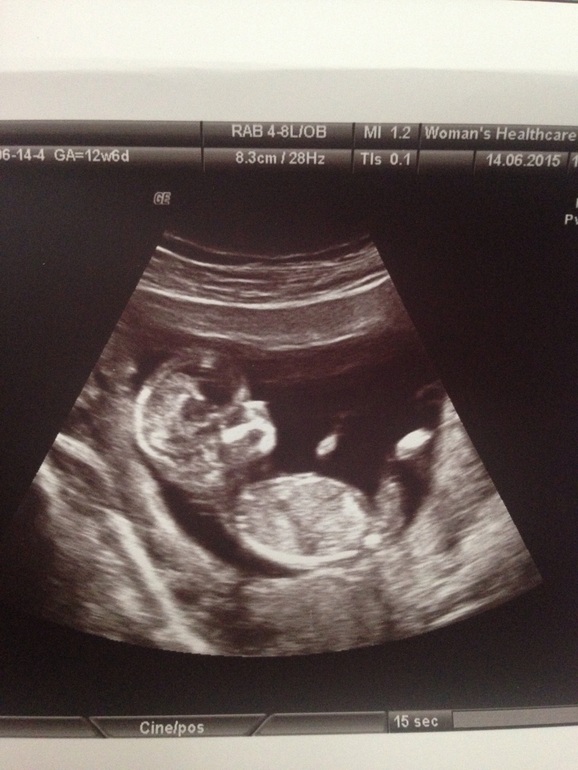

Сегодня, 14 июля мы всей семьей ездили на УЗИ. Муж был восторге от увиденного, сказал "маленький человечек":) У нас все хорошо, по размеру КТР 68, соответсвует 12 нед. и 6 дням( 13 нед.), дата родов перенесли на 20 декабря:) ЧСС 160 ударов, пол 50/50, и бугорок похожий на писюна увидели и половые губы тоже видели и все это под разными углами:)) так что ждем 2 УЗИ. Гематома моя исчезла, чему я безумно рада😆малыш сумел победить её, а я очень верю в своего малыша😍👣❤️Шейка матки 36-37, через 10 дней сново нужно проверить( после операции).😘

Мы вчера скрининг первый пришли) по месячным 12 и 6, по скринингу 13,2 поставили. КТР 71 мм, сердечко 156) сказали все в норме, кровь тоже сдали) но пока дату родов мне не корректировали, на 25 декабря . Поздравляю вас, знаю, насколько это важный день был)))